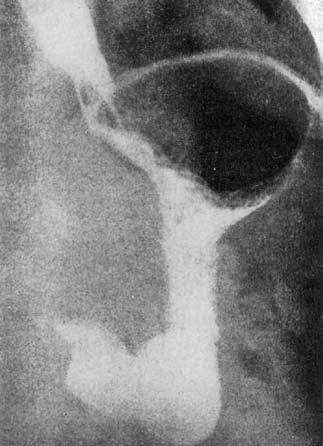

Рис. 19. Рентгенологические симптомы кардиоспазма: А – пищевод значительно расширен, удлинен и смещен вправо; дистальный его отрезок резко сужен, газовый пузырь желудка отсутствует; Б – справа в верхней доле легкого явления пневмосклероза как следствие многократных аспирационных пневмоний. (Приводится по: Е.М. Каган. Рентгенодиагностика заболеваний пищевода. М., 1968)